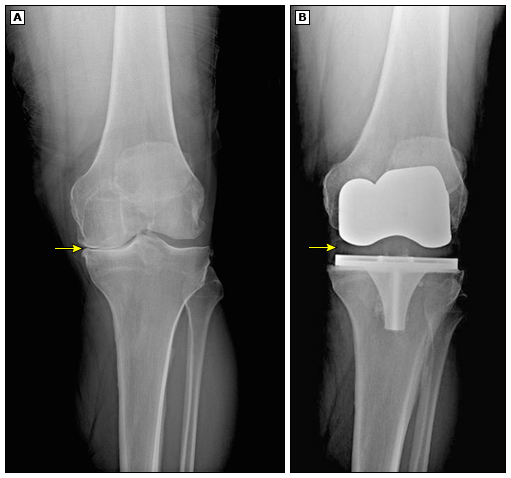

کی میتوانم مرخص شوم و چه مراقبتیهایی در طول بستری باید رعایت کنم؟ ترخیص شما بسته به زمان و نوع پروتز و تکنیک عمل جراحی بین دو تا هفت روز...